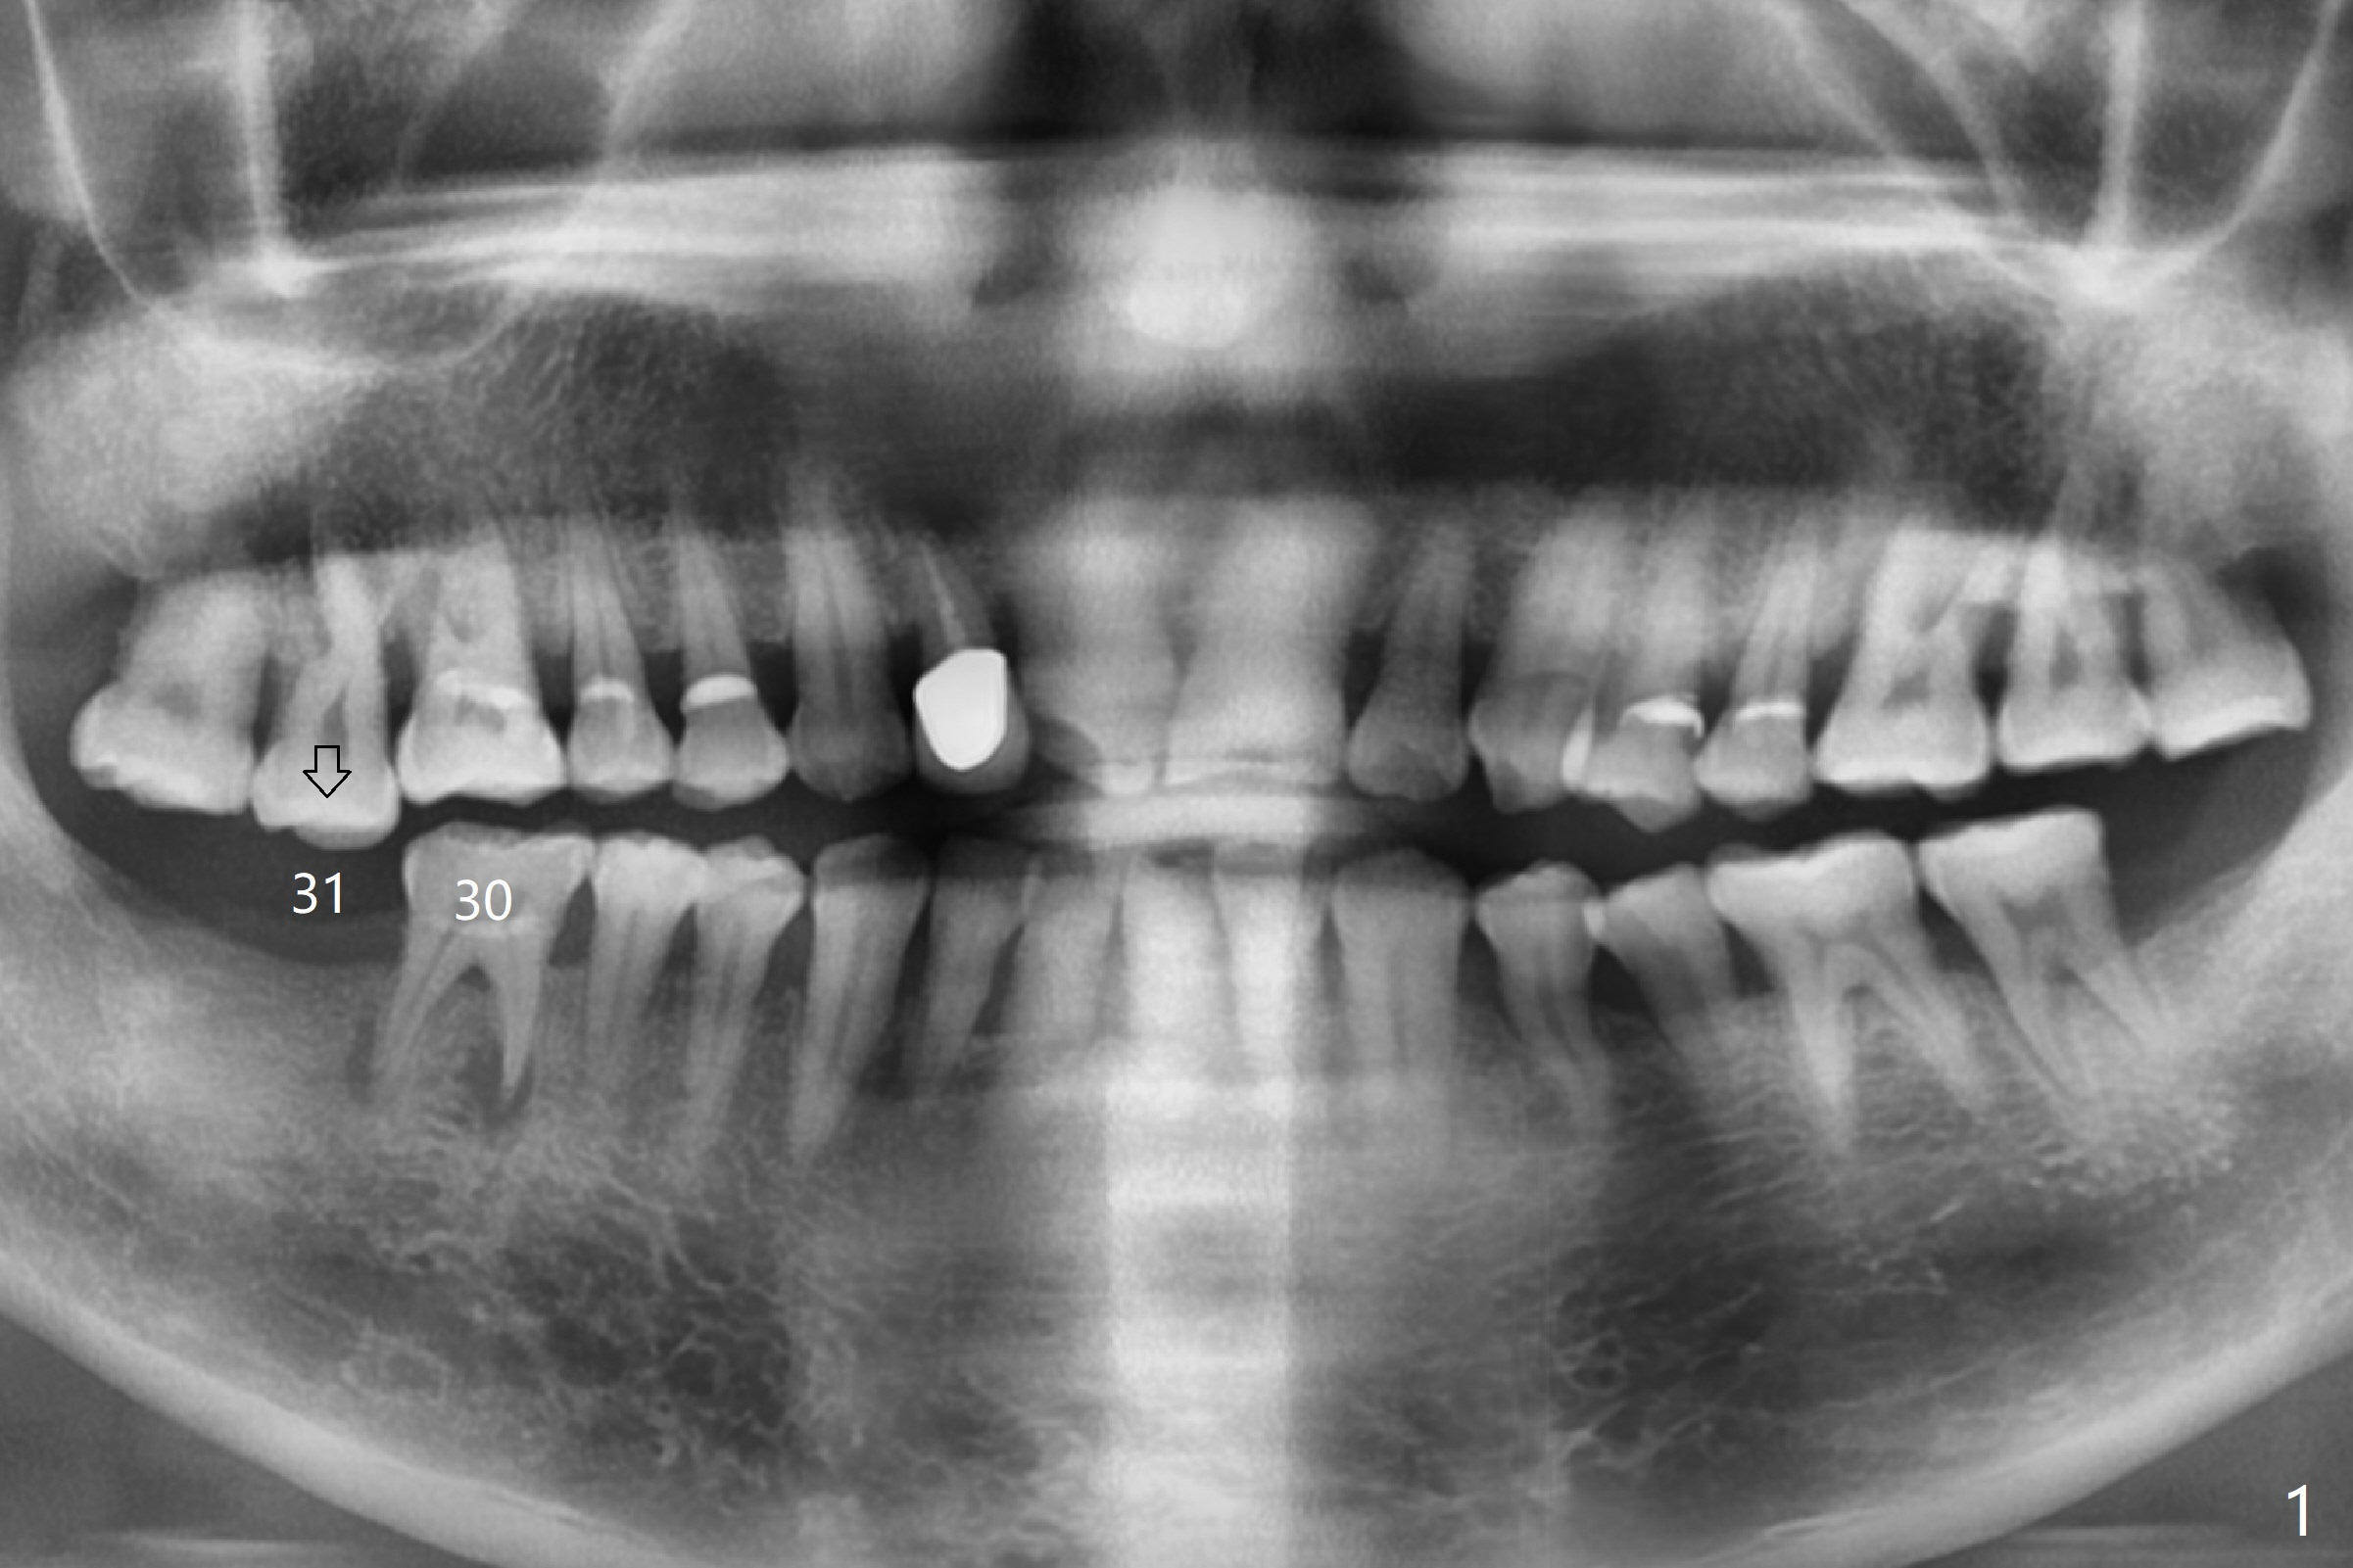

A 59-year-old man has subgingival fracture of the lingual cusps of the tooth #30 (Fig.1) with PARL, especially of the mesial root (Fig.2). An immediate implant will be placed slightly distolingually (Fig.3), while the delayed implant at #31 will be placed in a restorative position (Fig.4). Treat plan orthodontic intrusion of the tooth #2 if the latter is salvageable with periodontal lesion (Fig.1). Keep the tooth #1 in case bands and segmental wire are needed. It will be extracted prior to impression. After extraction, place a bony anchor pin at #31 for #30 osteotomy. When an implant is placed at #30, place a fixture anchor pin and finish osteotomy at #31.